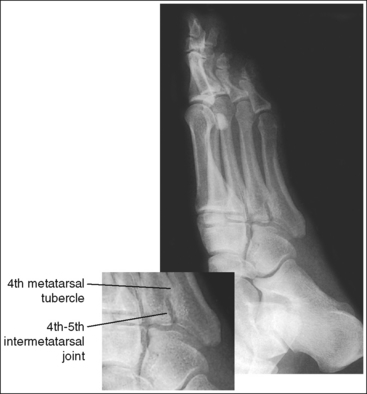

See Figures 6-17 and 6-18 and Box 6-6.

FIGURE 6-17 AP oblique foot projection with accurate positioning in a patient with a high longitudinal arch.

The foot demonstrates adequate obliquity. The cuboid-cuneiform joint space is open, the first and second intermetatarsal joints are closed, but the second through fifth intermetatarsal joint spaces are open, and the tarsi sinus and fifth metatarsal tuberosity are well demonstrated.

• To obtain an AP oblique foot projection, begin with the patient in a supine position with the knee flexed until the plantar foot surface rests against the receptor. Medially rotate the patient's leg and foot until the foot forms a 30- to 60-degree angle with the IR (Figure 6-19).

• Determining required obliquity. To determine whether a 30- or 60-degree rotation is needed, view the medial aspect of the patient's foot in an AP projection to judge the height of the patient's longitudinal arch. Less obliquity is required in a patient with a low longitudinal arch than in a patient with a high arch. If the patient has a low arch (Figure 6-20; also see Figure 6-15), rotate the patient's foot approximately 30 degrees medially; if the patient's foot has an average arch (Figure 6-21; also see Figure 6-16), rotate the foot approximately 45 degrees medially; and, if the patient's arch is high (Figure 6-22; also see Figure 6-17), rotate the foot approximately 60 degrees. The average arch requires 45 degrees of rotation. As the foot is rotated, keep the lower leg, ankle, and foot aligned to judge the degree of foot obliquity better.

• Judging the degree of the rotation on AP oblique foot projections. On lateral foot projections, the height of the longitudinal arches can be compared by evaluating the amount of cuboid demonstrated posterior to the navicular bone. Note that more cuboid is visible posterior to the navicular bone on the lateral foot projection in Figure 6-22 than in Figure 6-20 and Figure 6-23. A lateral foot projection from a patient with an average longitudinal arch demonstrates approximately 0.5 inch (1.25 cm) of cuboid posterior to the navicular bone, whereas a patient with a high arch will demonstrate approximately 0.75 inch (2 cm) and a patient with a low arch approximately 0.25 inch (0.6 cm). On AP oblique projections, accurate obliquity has been obtained when the cuboid-cuneiform and second through fifth intermetatarsal joint spaces are open. This accuracy is demonstrated on the AP oblique projections in Figures 6-17 and 6-21, even though they were taken with different degrees of obliquity. This can be confirmed by studying the amount of first and second metatarsal base superimposition, the amount of space demonstrated between the metatarsal heads, and the demonstration of the sinus tarsi (opening between the calcaneus and talus). When the foot is rotated medially, the first metatarsal base rotates beneath the second metatarsal base, and the second through third metatarsal heads move closer together. The greater the foot obliquity, the greater the superimposition of the metatarsal heads.

• Underrotation versus overrotation. If the degree of foot obliquity is inadequate for an AP oblique foot projection, the longitudinally running foot joints (cuneiform-cuboid, navicular-cuboid, and second through fifth intermetatarsal joint spaces) are closed. To determine whether the patient's foot has been underrotated or overrotated, evaluate the intermetatarsal joint spaces between the fourth and fifth metatarsals. If this joint space is closed and the fourth metatarsal base is superimposed over the fifth metatarsal base, the foot was underrotated (see Images 15 and 16). If the fourth-fifth intermetatarsal joint space is closed and the fifth proximal metatarsal is superimposed over the fourth metatarsal tubercle, the foot was overrotated (see Image 17). The fourth metatarsal tubercle is a rounded protruding surface located just distal to the fourth metatarsal base.